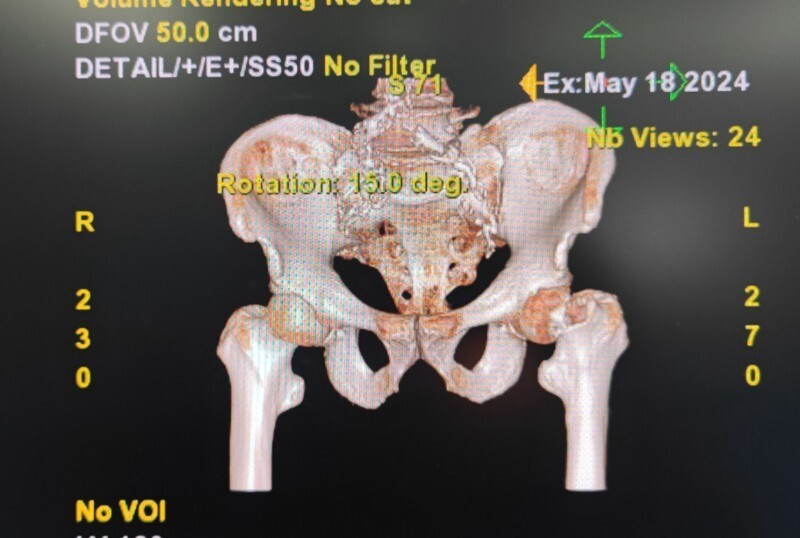

第2例:机器人辅助下全髋关节置换术

歙县人江某某,81岁,一周前在家中不慎摔倒后疼痛不已,被家人送来黄山新晨医院就诊,经过仔细检查后确认为“左股骨颈骨折”入院。

考虑到患者年龄较大,且基础疾病较多,骨科团队经过周密考虑讨论之后,建议其家属考虑机器人手术,在仔细了解手术机器人的相关知识后,其家属欣然接受,并表示江老先生很幸运,赶上了好机会。手术历经两个小时左右顺利结束,目前江老先生各项情况良好。